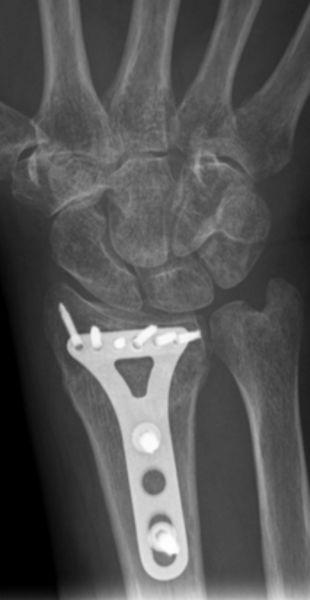

Flexionsfrakturen (Smith Frakturen) und instabile Brüche, sowie offene Brüche müssen operativ behandelt werden. Hierzu wird die Fraktur offen reponiert (eingerichtet) und mit einer Platte und darin einliegenden Schrauben in der korrekten Stellung gehalten. Heutzutage wird diese sogenannte Plattenosteosynthese (Verplattung) durch mittlerweile optimierte Materialien nahezu immer von der Handflächenseite (palmar) her eingebracht. Gelegentlich kann auch eine Versorgung mit Spickdrähten oder mit einem Fixateur externe (von außen aufgesetztes Metallgestell) besser zu Versorgung geeignet sein, der Operateur wird das jeweilige geeignete Verfahren auswählen.

Nach der Operation kann meistens direkt mit der krankengymnastischen Beübung des Handgelenks begonnen werden, allerdings darf das Handgelenk für in der Regel 6 Wochen nicht mit Gewicht belastet werden. Die Nachbehandlung wird individuell vom Operateur festgelegt werden und richtet sich nach verschiedenen Kriterien, unter anderem nach der Knochenqualität.